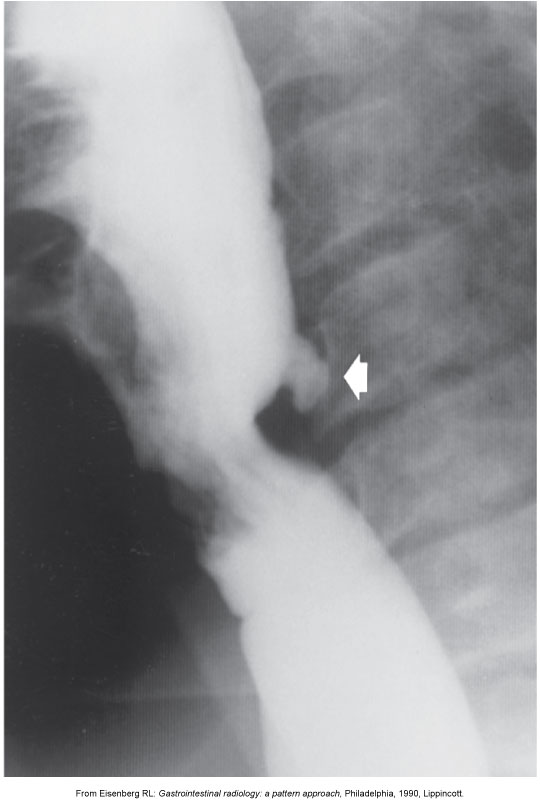

How do ulcers appear on contrast studies?

Appear as outpouchings due to surrounding mucosal edema (not true outpouchings).

How are ulcers classified by location?

Gastric (stomach) vs duodenal (duodenal bulb or pylorus).